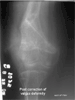

Result

At 6 months post last surgery, patient can ambulate independently without any pain in the knee. Patient claims no limitation from activities of daily living. Range of motion of the knee is progressively improving. Presently it is 0 to 100 degrees.